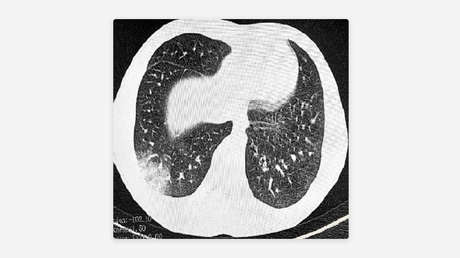

La EPOC se produce cuando los pulmones no dan abasto y la persona que la padece le cuesta respirar durante largos periodos de tiempo.